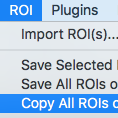

Easily represent and compute the PI-RADS v2.0 score, with a full graphic user interface. The score is assessed on prostate MRI. Images are obtained using a multi-parametric technique including T2 weighted images, a dynamic contrast study (DCE) and DWI. The goal of PI-RADS score is to improve diagnosis and treatment of prostate cancer. The plugin produces a complete report, including diagrams, in high quality DICOM PDF format.

Learn more in the PI-RADS v2.0 Report Plugin User Manual.